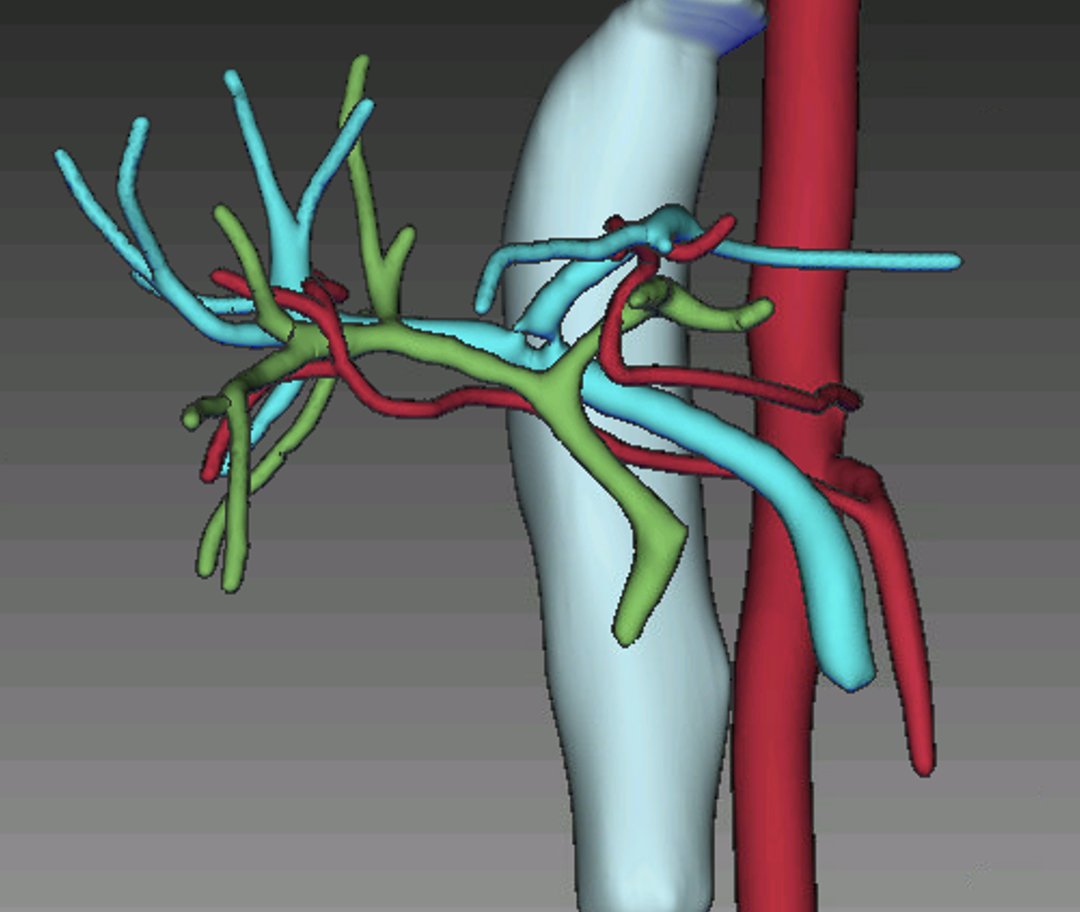

Completed another robotic donor right hepatectomy with @BenSamstein. This time we invited @JHawksworthMD to maximize our 🤖LD experience on both campuses. 👉 https://t.co/wL9GLYyVe9 (different case) @WCMSurgery @ColumbiaSurgery @ILLS_LAPLIVER @ASTSChimera